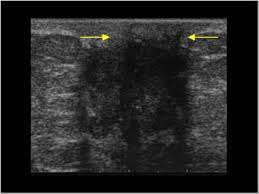

Breast ultrasound is not usually done to screen for breast cancer. What does a breast cancer lump look like? We also describe the various types and treatment options. Hi, breast ultrasound is a procedure that may be used to determine whether a lump is a cyst (sac containing fluid) or a solid mass. Combined screening with ultrasound and mammography vs mammography alone in women at elevated risk of breast cancer.

Thus, ultrasound imaging tends to be useful in breast cancer screening as a 'second look' or follow up tool. Breast cancer can develop in males and females, but due to differences in breast tissue, the disease is much less common in males. Does a lung mass mean you have cancer? Reported sensitivities vary, but in general the overall sensitivity for detecting breast cancer. Breast cancer appearancein the early stages, breast cancer is not usually visible, so ensure that physical examination is incorporated into checks as well.

Breast ultrasound uses sound waves to make a computer picture of the inside of the breast.